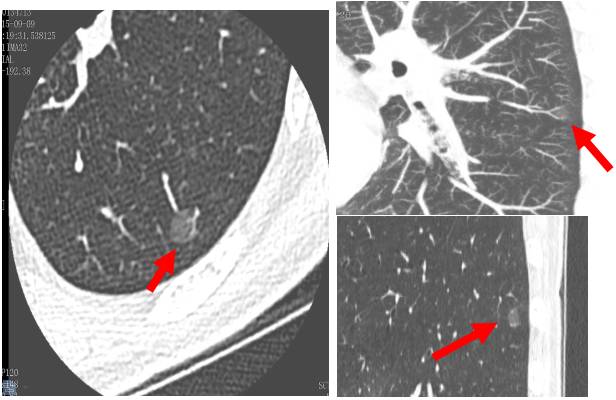

過(guò)去,常見(jiàn)的肺癌檢查工具是只有胸部X光檢查,但它很難看出1cm以下的結(jié)節(jié)。隨著肺癌診斷技術(shù)的發(fā)展,低劑量螺旋CT(LDCT)掃描目前已經(jīng)成為早期肺癌篩查的最佳方法。并得到全球醫(yī)師的認(rèn)可和遵循,美國(guó)于2011年和2015年兩次將其列入肺癌NCCN指南中。 我國(guó)在2015年也把LDCT列入早期肺癌篩查,并做了規(guī)范與共識(shí),同年5月在中華放射學(xué)雜志第49卷第5期發(fā)表了該規(guī)范與共識(shí)。

美國(guó)曾有一項(xiàng)針對(duì)50至74歲有抽煙病史民眾的大規(guī)模肺癌篩檢。研究顯示,低劑量螺旋CT有助于發(fā)現(xiàn)早期肺癌,特別是周?chē)头切〖?xì)胞肺癌,其檢出率約為胸部X光的10倍。

并且,相較于胸部X光檢查,低劑量CT掃描可降低20%肺癌死亡率。研究證實(shí)了低劑量CT的年度篩查可發(fā)現(xiàn)85%的Ⅰ期肺癌,其后手術(shù)切除的10年生存率達(dá)92%。

基線第1次LDCT篩查,年度復(fù)查L(zhǎng)DCT。隨診LDCT基線掃描以后,檢查出的肺內(nèi)結(jié)節(jié)需在1-12個(gè)月內(nèi)進(jìn)行LDCT復(fù)查,具體根據(jù)病灶大小及實(shí)性等情況來(lái)定。一般最晚不能超過(guò)12個(gè)月。